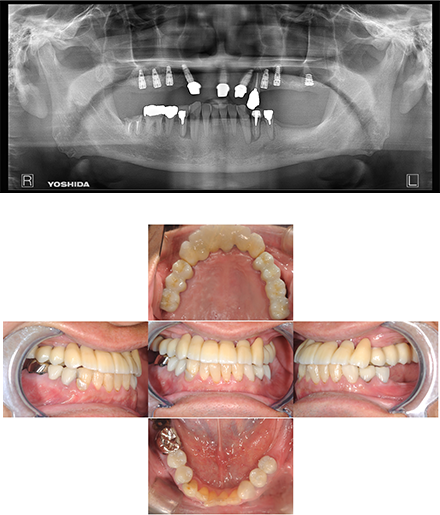

かわま歯科では、とりあえず痛みを取る、見た目だけをきれいにするというようような、その場しのぎの治療はいたしません。インプラント、セラミック治療、歯列矯正においても、見た目と機能面の両方で妥協せず、患者さんにとって最も有益な治療をご提案いたします。また、徹底したカウンセリングと治療計画を基に、歯科医師と患者さんが共通のゴールを確認できてから、初めて治療をスタートいたします。